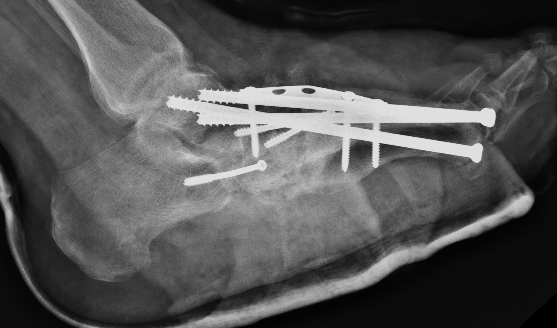

Midfoot Osteotomy and Arthrodesis

Options

Plates

Intramedullary screws

Technique

Superconstructs (4 concepts)

1. Fusion is extended beyond the zone of injury to bridge the area of bony dissolution

2. Aggressive bone resection - allows reduction of deformity with reduced soft tissue tension

3. Stronger implants - medial / central and lateral column fixation

4. Load sharing devices

- intramedullary beams

- axial screw fixation from 1st MTPJ through metatarsal into talus

- also IM screw through 2nd and 3rd metatarsal into talus